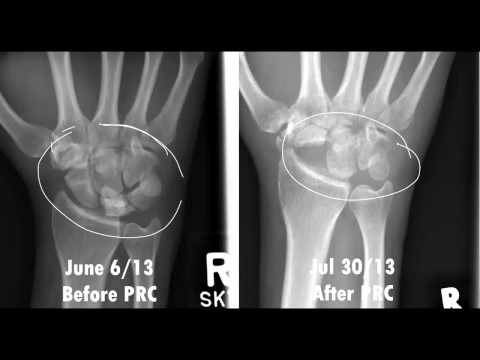

Proximal row carpectomy treatment, etiology, epidemiology, natural history, anatomy, symptoms, xrays, classification, complications and references. 552 x 634 png 191 кб. Proximal row carpectomy is a salvage procedure for a variety of wrist problems that is generally only used when other less invasive options. Proximal row carpectomy provides painless. This operation has not been that popular in the uk but has been more so on the continent particularly in the nederlands and belgium prximal row carpectomy (prc) involves removing the first row of the carpal bones which consists of the scaphoid, lunate and trquetrum. Proximal row carpectomy with total scapoidectomy vs. Proximal row carpectomy (prc) is one of several surgical options for patients with advanced wrist arthritis. The proximal row carpectomy has been performed removing the scaphoid, lunate and triquetrum leaving a space for the graft to be inserted. Procedure 86 proximal row carpectomy. Learn the proximal row carpectomy (for advanced arthritic wrist pain) surgical technique with step by step instructions on orthoracle. Proximal row carpectomy 8 weeks later. Published on 17/04/2015 by admin. High complication rates in total wrist arthroplasty (twa) still lead to controversy in the medical literature, and novel methods for complication reduction are warranted.

Proximal row carpectomy with total scapoidectomy vs. The proximal row carpectomy has been performed removing the scaphoid, lunate and triquetrum leaving a space for the graft to be inserted. This operation has not been that popular in the uk but has been more so on the continent particularly in the nederlands and belgium prximal row carpectomy (prc) involves removing the first row of the carpal bones which consists of the scaphoid, lunate and trquetrum. The loss of a hand is a devastating but not so common injury with a huge array of effects. Proximal row carpectomy, slac wrist, snac wrist, avascular necrosis of the lunate bone. Proximal row carpectomy treatment, etiology, epidemiology, natural history, anatomy, symptoms, xrays, classification, complications and references. This is a detailed step by step instruction through a proximal row carpectomy (prc), a procedure in which the proximal row of carpal bones. Learn the proximal row carpectomy (for advanced arthritic wrist pain) surgical technique with step by step instructions on orthoracle.

Proximal row carpectomy is a surgical procedure of the wrist where an entire row of wrist bones are removed.